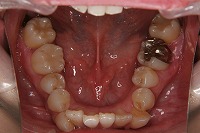

28歳6ヵ月

下顎

前歯が出ていて歯並びが悪い事を主訴に来院された、26歳1か月の女性です。診断「歯と歯槽基底の大きさの不調和による叢生」上顎は右側第1小臼歯と左側の犬歯、下顎は抜歯をせず治療を行いました。